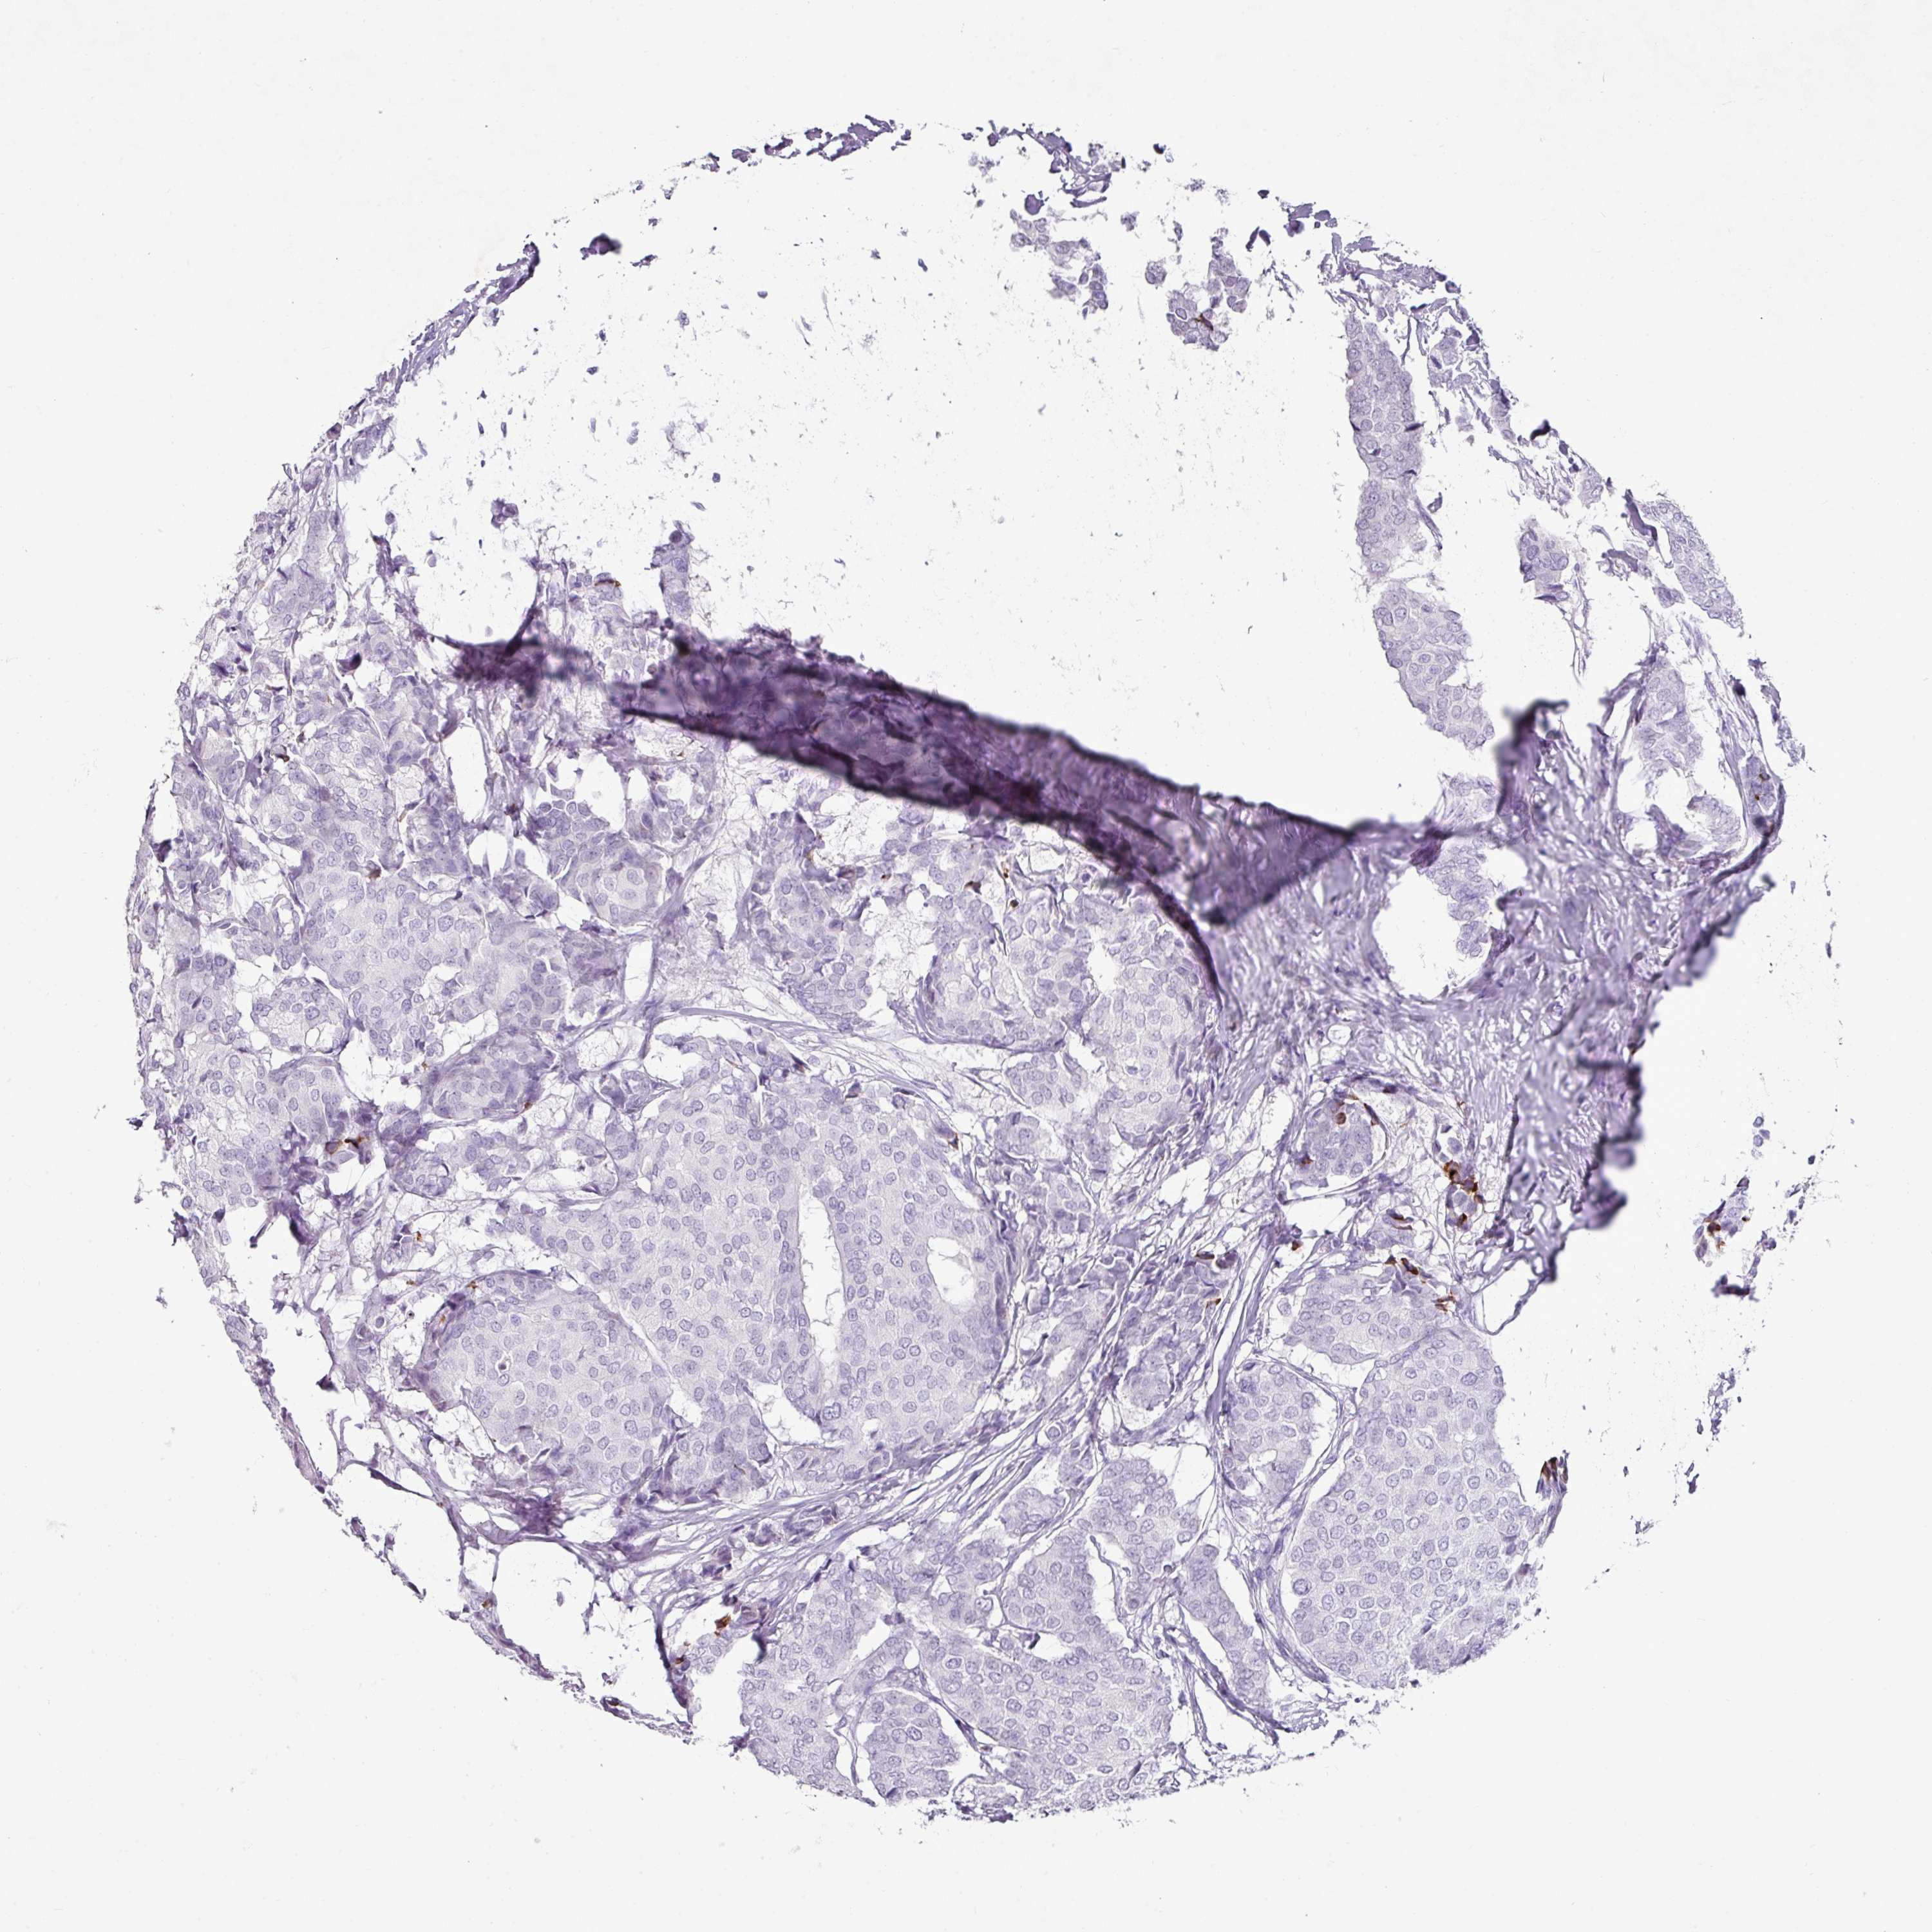

CANCER BREAST CANCER Show tissue menu

BRCA TCGA BRCA VALIDATION PROTEIN EXPRESSION